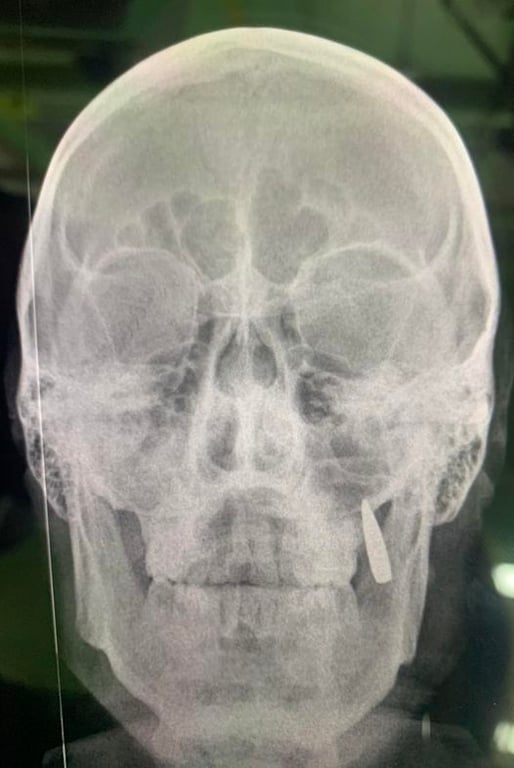

У бійця Збройних сил України у щелепі застрягла куля. Він дізнався про це лише тоді, коли робив рентген.

Військовий розповів, що йому щось вдарило в щоку та вибило два зуби. Зокрема, він переживав, що згодом треба до стоматолога.

"Оглядаємо легких, один каже, що дайте покурити та відпустіть назад на позиції, тільки гляньте, бо щось вдарило в щоку (на цьому місці невеликий поріз без кровотечі), вибило два зуба. Переживає, що згодом треба до стоматолога їхати... Робимо рентген, замість двох зубів у щелепі застрягла куля", — написала волонтерка.

Також вона опублікувала рентгенівський знімок, на якому можна побачити кулю в щелепі.

Де і коли це сталось — інформації немає. Відомо лише місце — прифронтовий стабпункт.